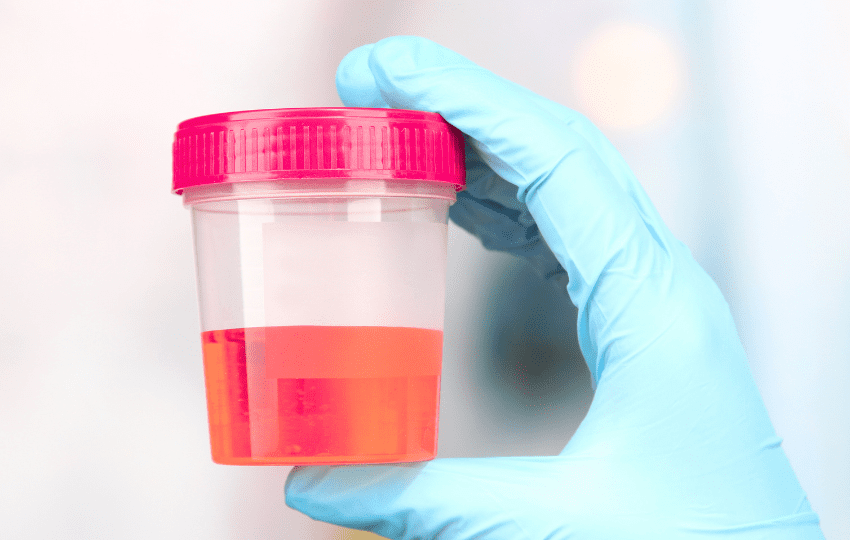

É importante destacar que a droga é pouco absorvida sistemicamente, sendo eliminada quase integralmente pela urina (98,6% inalterada). Essa característica explica a predominância de efeitos adversos locais em detrimento de toxicidades sistêmicas.

As reações descritas concentram-se no trato urinário inferior, destacando-se:

- Irritação vesical, com dor, urgência, frequência aumentada, disúria e espasmos.

- Hematúria.

- Infecções urinárias recorrentes.

- Incontinência urinária transitória.

- Alteração da coloração da urina (vermelha) nas primeiras 24 horas após a instilação.

Embora raras, reações de hipersensibilidade podem ocorrer devido ao veículo da formulação